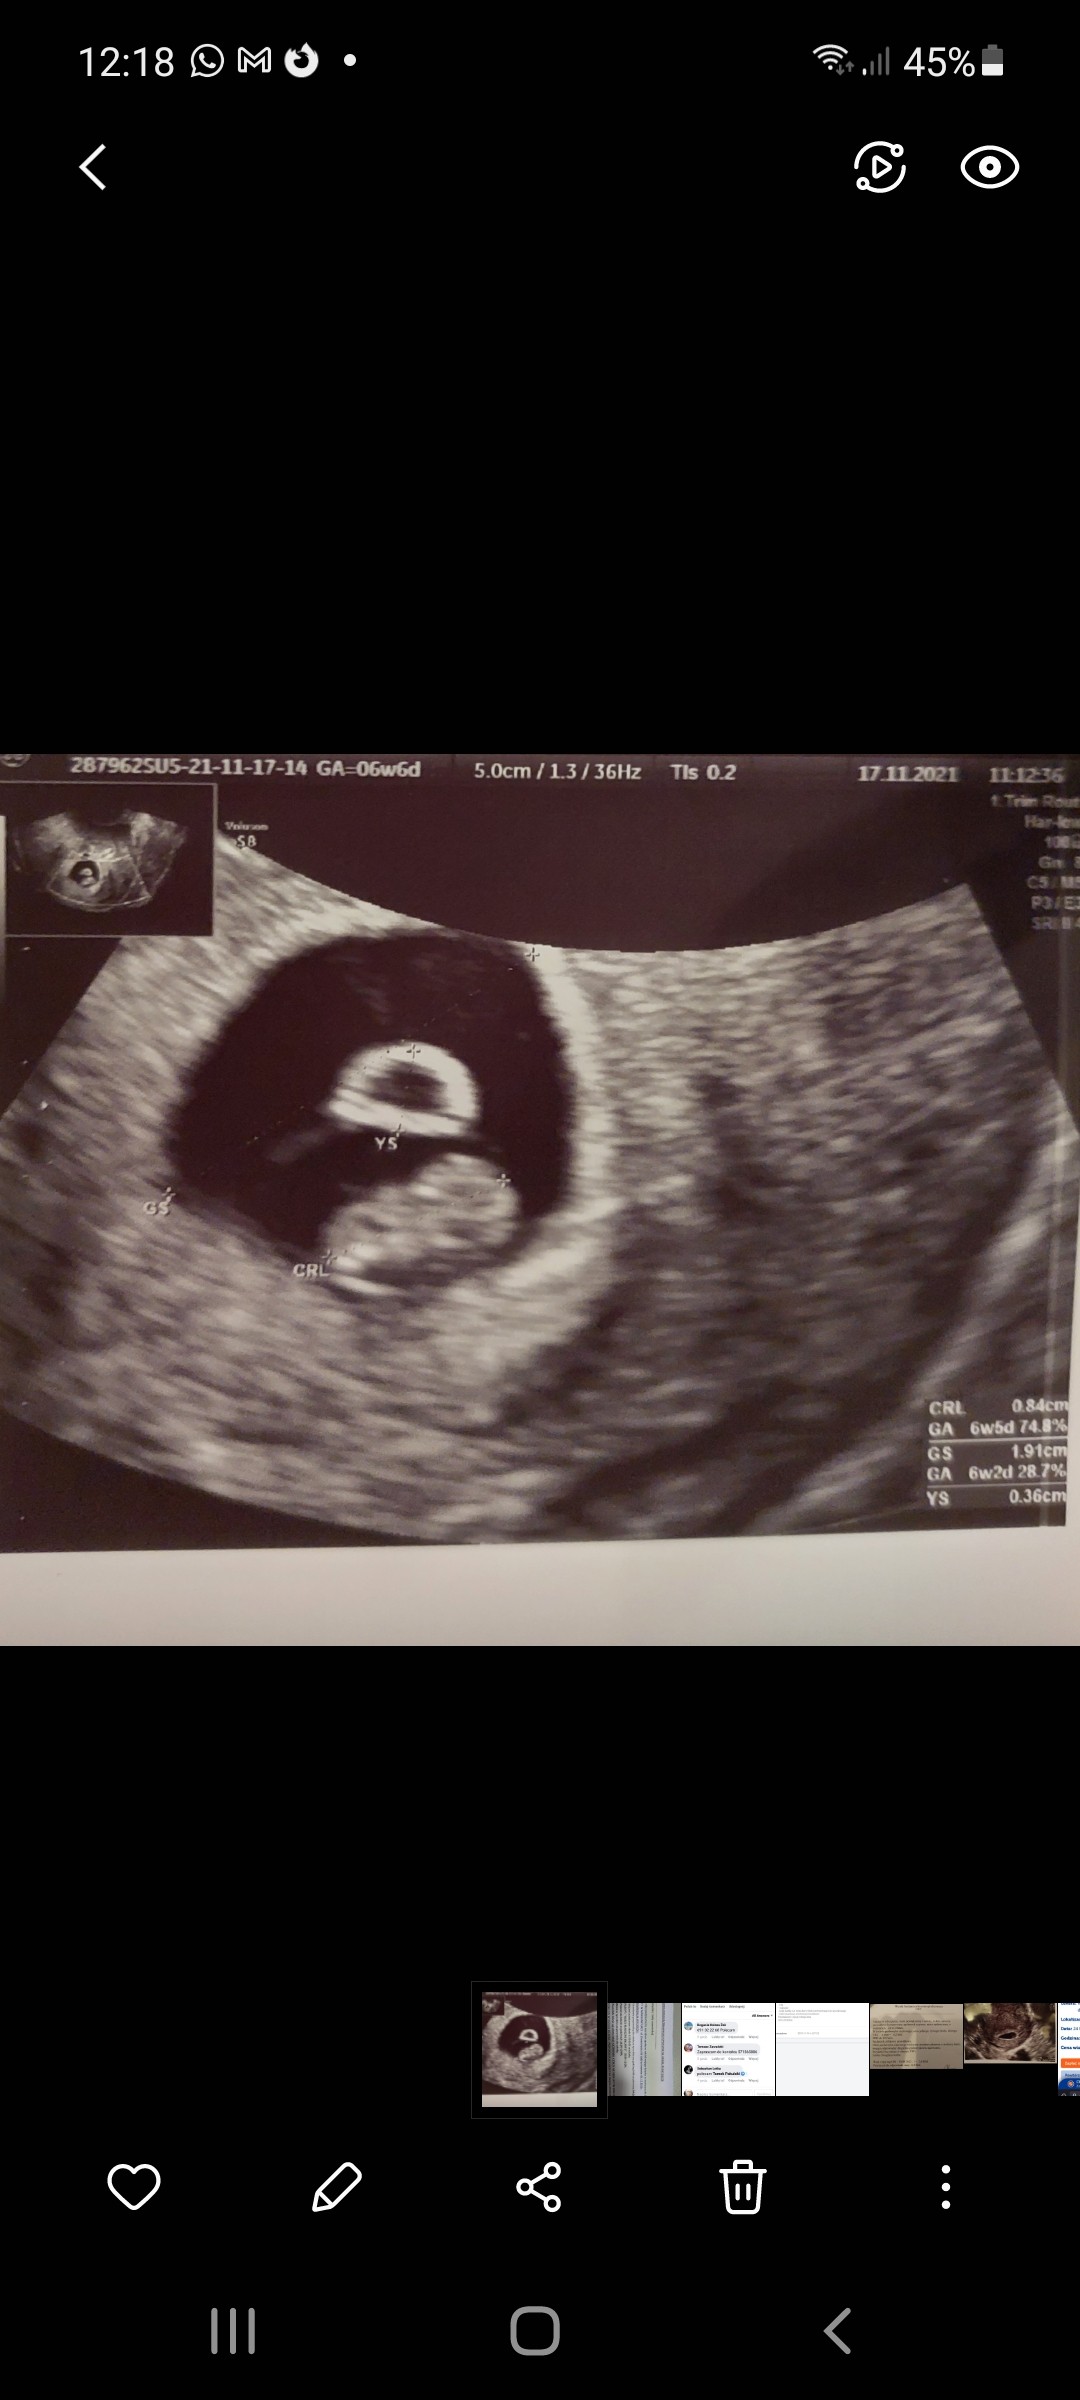

Wróciłam z wizyty.

Serduszko nadal bije. Pani doktor powiedziała, że w dobrym tempie, prawidłowo. Pęcherzyk tym razem okrąglutki, więc leżenie pomogło na poprawę jego kształtu.

Dostałam skierowanie na badania prenatalne. Wyznaczono mi termin na 27.12. To bedzie skończony 12tc i 4d.

Załączniki

• Screenshot_20211117-121831_Gallery.jpg

Screenshot_20211117-121831_Gallery.jpg

223,7 KB · Wyświetleń: 98